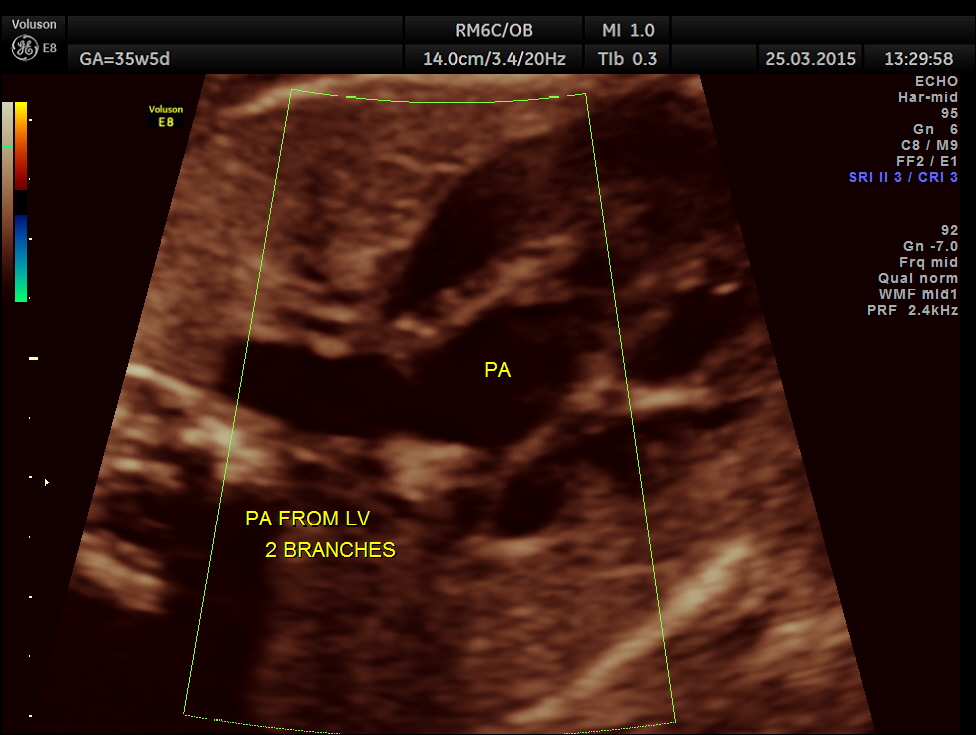

The artery coming out of left ventricle branches into two – suggestive of pulmonary artery.

The great artery arising from the LV branches into two suggestive of pulmonary artery.